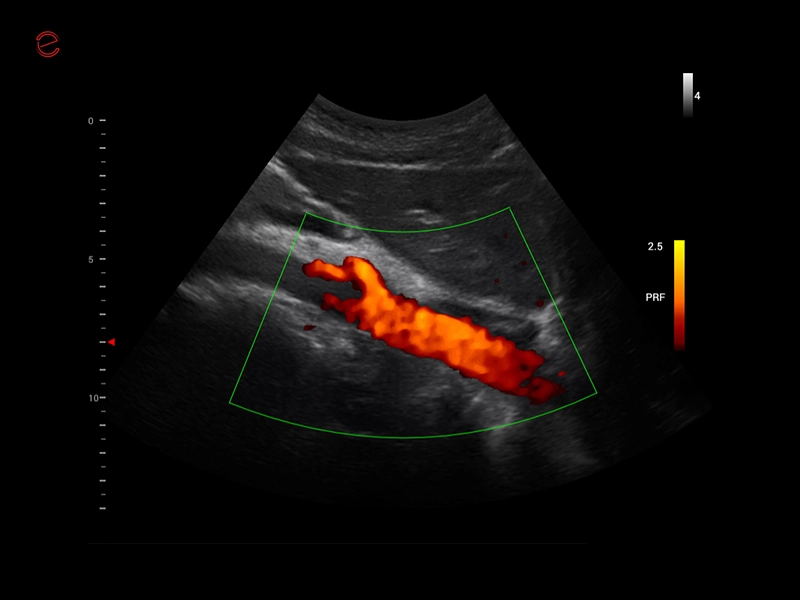

MyLab™X1 Go - GI Abdo CFM

MyLab™X1 Go - GI Abdo CFM